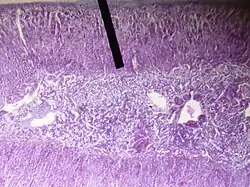

The zona reticularis (sometimes, reticulate zone) is the innermost layer of the adrenal cortex, lying deep to the zona fasciculata and superficial to the adrenal medulla. The cells are arranged cords that project in different directions giving a net-like appearance (L. reticulum - net).[1]